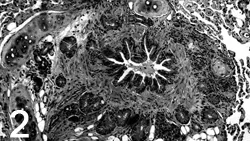

The most common radiographic change common to both feline asthma and bronchitis is peribronchial cuffing, often described as doughnuts or tram lines (Figure 1). Other common causes of cough and increased respiratory effort include pneumonia, heart failure, cancer, and heartworm disease. These disorders usually create radiographic abnormalities that differ from the classic findings of hyperinflation and bronchial markings seen in chronic bronchitis or asthma.

Figure 1. This lateral thoracic radiograph demonstrates classic features of feline asthma, including hyperinflation and peribronchial infiltration (doughnuts and tram lines).